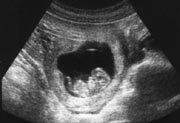

超音波で見た10週の胎児。

このような超音波検査で、妊娠9、10、11週に赤ちゃんの頭からおしりの長さを測り、妊娠予定日を出します。

妊娠8週からは「胎芽(たいが)」を卒業して「胎児」になります。赤ちゃんは子宮の中で体を丸めているので、身長を測ることができません。CRL(頭殿長)といって、頭からおしりまでの長さ(座高)を測ります。